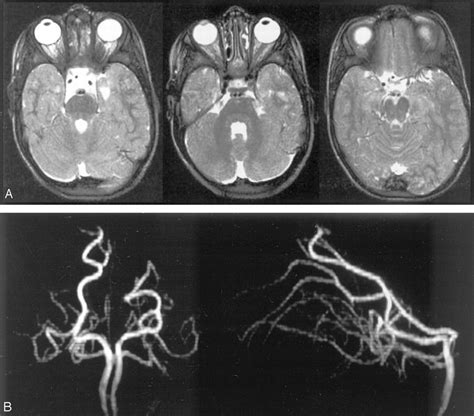

Diagnosis and Emergency Imaging

When a patient arrives at the emergency department with suspected neurological deficits, medical professionals follow a strict protocol. Speed is the priority. Doctors will typically perform a neurological exam and immediately order imaging studies to differentiate between an ischemic stroke and a hemorrhagic stroke.

• Magnetic Resonance Imaging (MRI): More sensitive than a CT scan for detecting early signs of ischemia in the brainstem.

• Magnetic Resonance Angiography (MRA): Similar to CTA, it maps the blood vessels without the need for iodinated contrast in some cases.